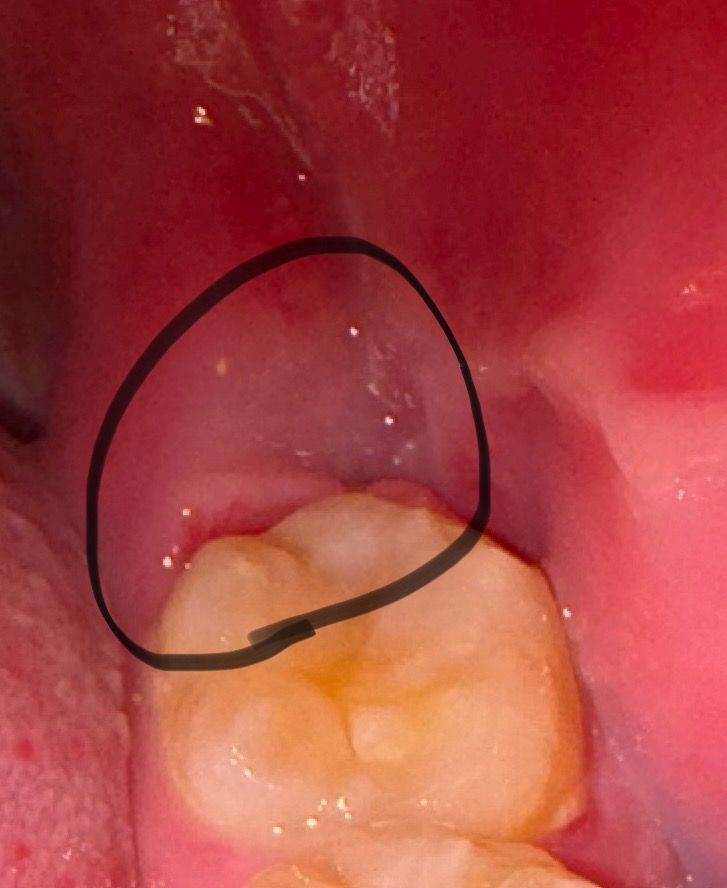

2주전 매복 사랑니 발치를 했는데 잇몸리 들려있는데 왜 그런건가요?

매복사랑니가 올라오면서 잇몸이들려있길래 발치를 진행했습니다

하지만 2주 지났는데도 저렇게 벌어져있는데 물 가글할때마다 불편하네요.. 왜 이런건가요?

잇몸이 아직 다 아물지 않아서 그렇스니다. 시간지 지나면서 잇몸은 아무니 너무 걱정하지 않으셔도 될것같습니다.

아직 잇몸 초기치유가 완전히 되진 않았습니다 조금 더 시간이 필요할 것 같습니다 완전히 치유부전의 양상이나 출혈이 멈추지 않거나 통증이 지속되는 것은 아니므로 너무 걱정하진 않으셔도 됩니다